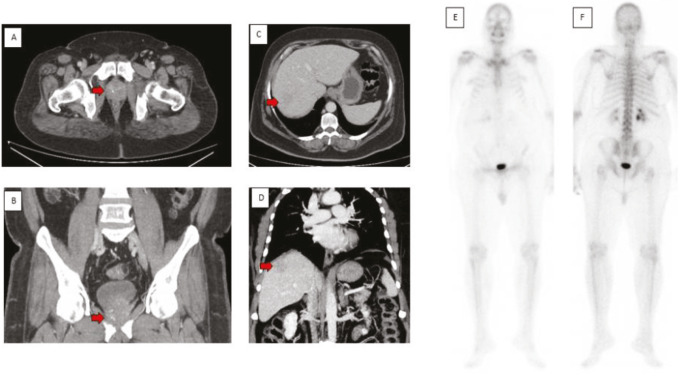

镓-68前列腺特异性膜抗原正电子发射断层扫描联合计算机断层扫描(68Ga PSMA PET-CT)是一种受体特异性成像,越来越多地用于前列腺癌(PCa)的分期和再分期。PSMA是在正常前列腺组织细胞质中表达的II型跨膜糖蛋白,在前列腺癌中超表达100-1000倍。它也在移行细胞癌、肾细胞癌、肝细胞癌、甲状腺癌和脑癌等非前列腺实体瘤的肿瘤相关新血管内皮中表达。我们在此提出一个病例,PSMA PET扫描显示三个肿瘤证实在随访成像。

Galium-68 prostate-specific membrane antigen positron emission tomography combined with computed tomography (68Ga PSMA PET-CT) is receptor specific imaging, which has increasingly been used in the staging and restaging of prostate carcinoma (PCa). PSMA is type II transmembrane glycoprotein expressed in cytosol of normal prostatic tissue with 100-1000-fold over expression in PCa. It is also expressed in the endothelium of tumor-associated neo vasculature of non-prostatic solid tumor such as transitional cell and renal cell carcinoma, hepatocellular, thyroid, and brain cancers. We hereby present a case where PSMA PET scan showed three tumors proved on follow up imaging.